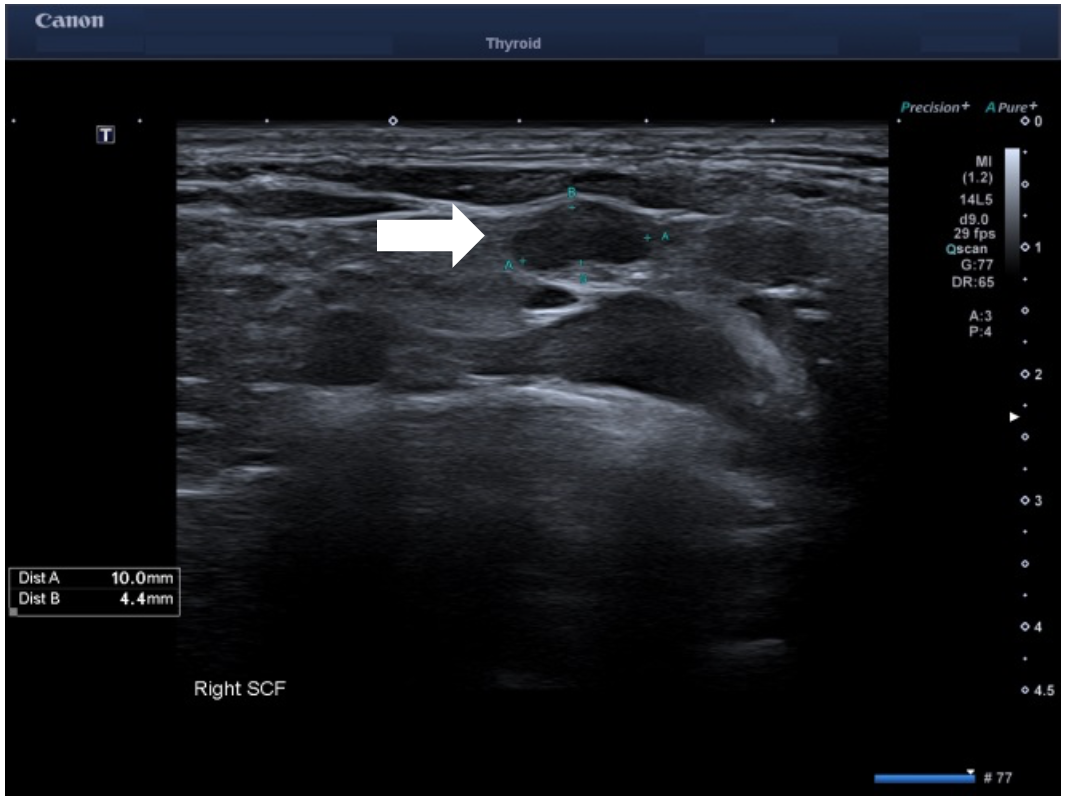

Owing to the aggressive cancer in a young patient, a staging PET/CT study was performed which showed a small but metabolically active lymph node in the right supraclavicular fossa. An US of the supraclavicular fossa revealed several small volume nodes. The most prominent 10 x 4 mm node had a normal architecture but with only mild cortical thickening. Power Doppler imaging (PDI) and color Doppler imaging (CDI) showed feeding vessels but otherwise no suspicious features. However, on using Superb Microvascular Imaging monochrome (SMI), this revealed abnormal peripheral vascularity which was best depicted in the monochrome mode. This feature made the node suspicious for malignancy and corresponded to the FDG avid node on the PET study. Subsequent fine needle aspirate of the right supraclavicular node confirmed metastatic disease.

Longitudinal ultrasound of right supraclavicular fossa showed a small 10 x 4 mm lymph node in the right supraclavicular fossa (SCF) with mild cortical thickening. SMI revealed abnormal peripheral vascularity which made it suspicious for metastatic infiltration and most likely represented the metabolically active SCF node on the recent PET imaging.